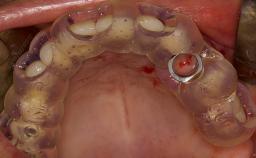

Following tooth loss, alveolar resorption and ongoing pneumatization of the maxillary sinus may lead to vertical and horizontal bone deficits in the posterior maxilla.

This deficit reduces the distance between the maxillary sinus floor and the alveolar process, so that reconstructing the vertical bone height by means of a sinus floor elevation procedure may be a prerequisite for placement of dental implants of the correct dimensions and in the ideal three-dimensional positions in order to achieve optimal functional and esthetic treatment outcomes while respecting relevant anatomical structures.